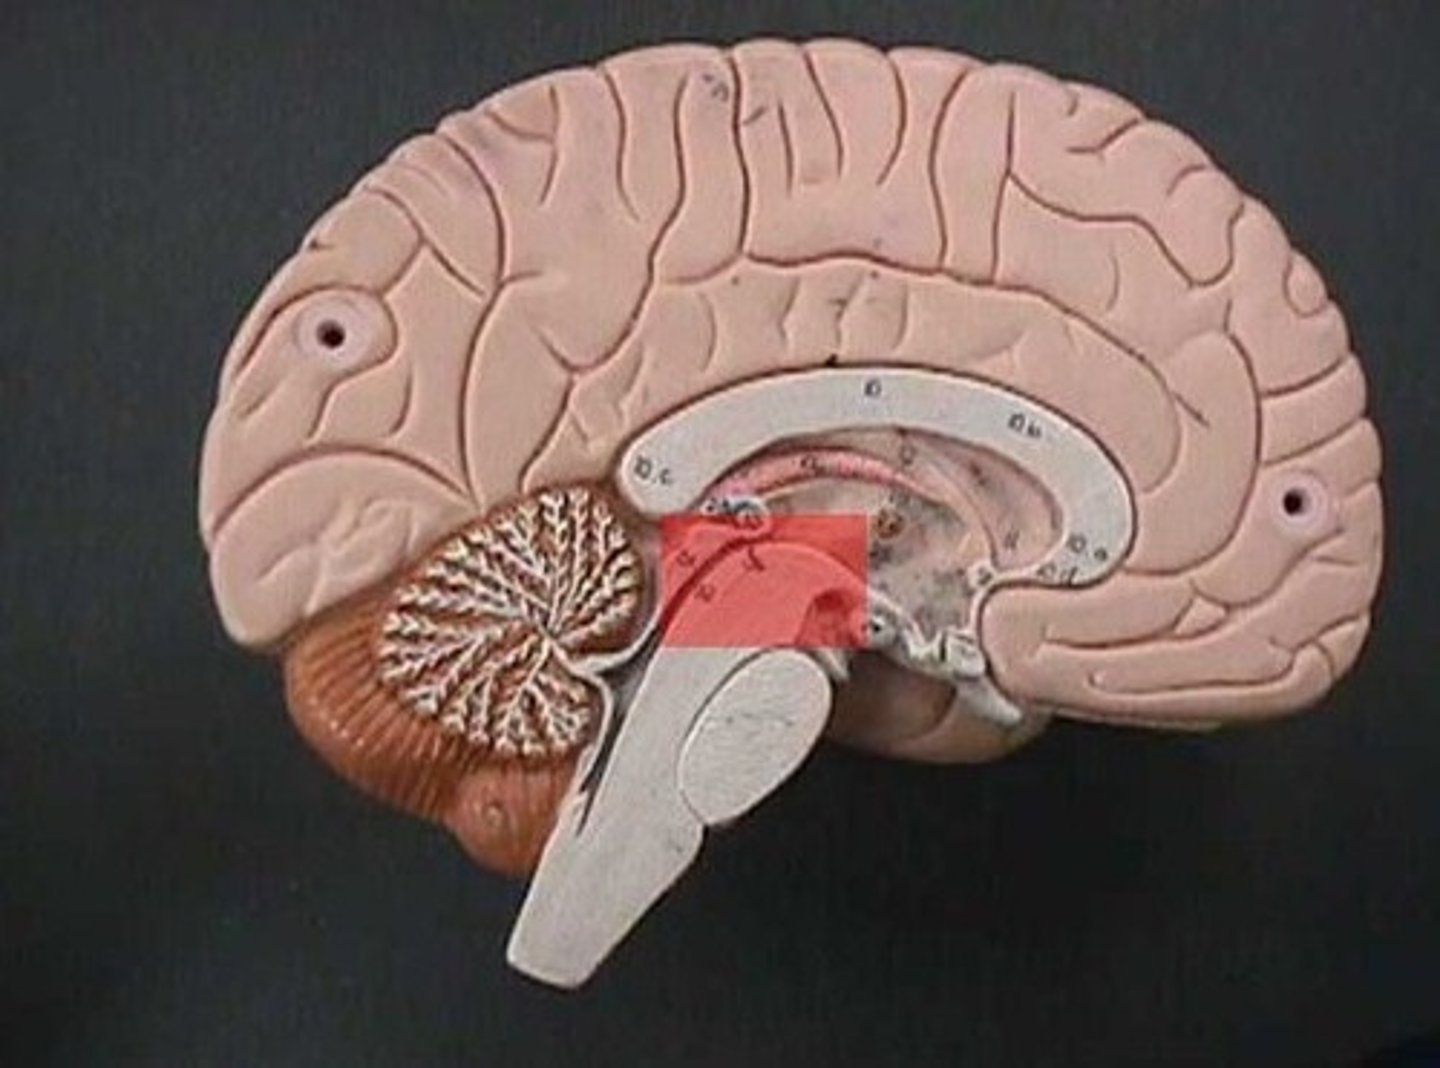

medulla oblongata

basic life support, heart beating, etc.

decussation of pyramids

where the cleavage furrow becomes almost flat - the reason for contralateral control

pons

control of breathing

midbrain

immediate reflexes

cerebral peduncles

connect lower and upper brain, cerebrum to brainstem

corpora quadrigemina

located in the midbrain; contains reflex centers for vision and auditory reflexes.

superior colliculi

part of corpora quadrigemina, visual reflexes

inferior colliculi

part of corpora quadrigemina, auditory reflexes

diencephalon

thalamus and hypothalamus

thalamus

relay station for all somatosensory information

intermediate mass

connection between the two thalami across the third ventricle, dumbbell shape

hypothalamus

brain region (many nuclei) in charge of maintaining homeostasis

pituitary gland

produces hormones

mammillary bodies

olfactory relay stations

epithalamus

region above midbrain that contains pineal gland

pineal gland

regulates sleep-wake cycles, secretes melatonin

cerebellum

balance, equilibrium, gross motor movement

vermis (cerebellum)

The tissue between the two cerebellar hemispheres

arbor vitae

"tree of life," white matter of cerebellum